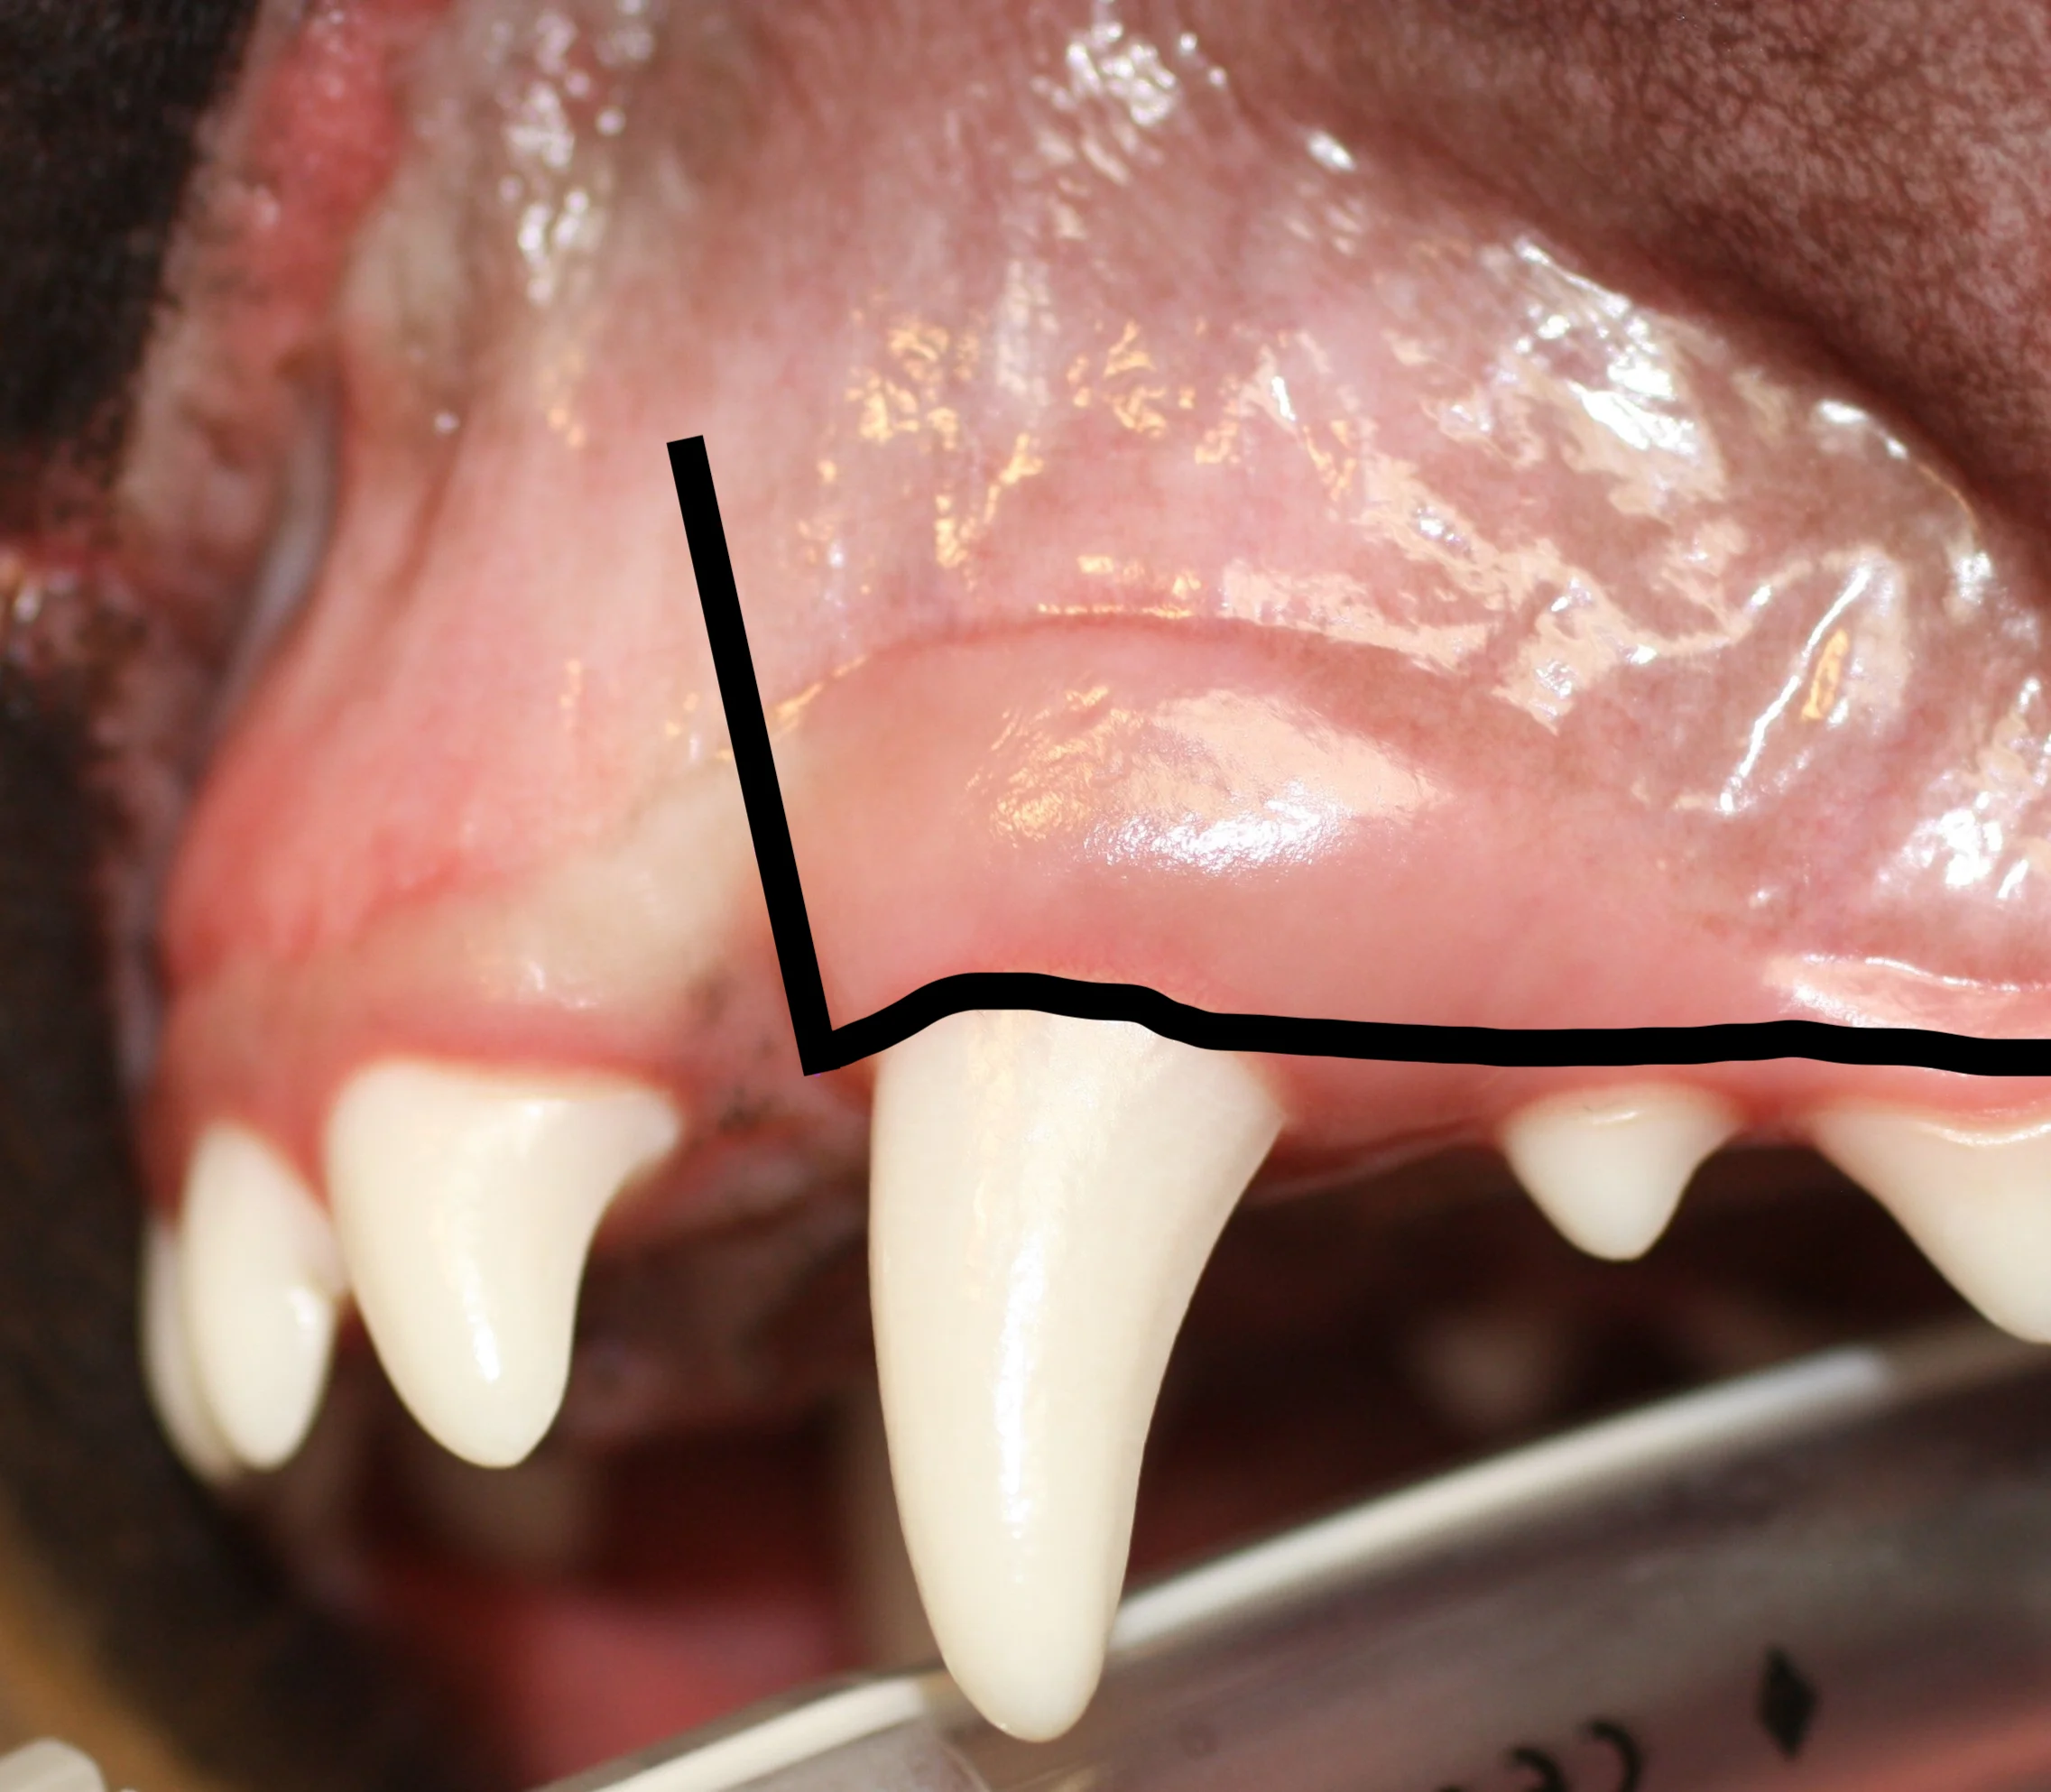

Triangular Flap

A triangular flap is created by making a mesial releasing incision and an incision at the ventral alveolar border (line). The releasing incision should extend at least to the level of the widest part of the root.

Envelope Flap

An envelope flap is created by making an incision at the ventral alveolar border (line). This type of flap may be preferred because vertical releasing incisions can contribute to complications (eg, dehiscence).